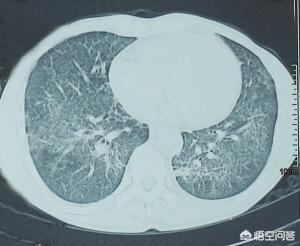

3. la pneumonie à Pneumocystis carinii

Les symptômes comprennent l'essoufflement, la fièvre et la toux sèche, dont l'essoufflement et la toux sèche sont spécifiques. Les patients atteints du SIDA ont une évolution lente et progressive, commençant par une perte de masse corporelle, des sueurs nocturnes, une hypertrophie des ganglions lymphatiques et un malaise général, suivis par les symptômes respiratoires décrits ci-dessus, qui peuvent durer des semaines, voire des mois. 100 % des décès non traités sont dus à une insuffisance respiratoire. La maladie est très symptomatique, mais les signes pulmonaires sont rares et la plupart des patients ne présentent aucune anomalie à l'auscultation des poumons.

- Pneumonie à Pneumocystis carinii

Les principaux symptômes sont les suivants : fièvre, toux sèche, oppression thoracique et dyspnée s'aggravant progressivement.

Le stade avancé du SIDA est principalement dû au déclin de la fonction immunitaire, ce qui facilite le développement de toutes sortes d'infections. Certains agents pathogènes qui n'affectent pas les personnes ordinaires provoquent des maladies mortelles chez les patients au stade avancé du SIDA, par exemple la pneumonie à Pneumocystis carinii, dont les principaux symptômes sont la fièvre, la toux sèche, et qui, si elle n'est pas traitée, entraînera bientôt une hypoxie, un essoufflement après une activité, voire une incapacité totale à se mouvoir.